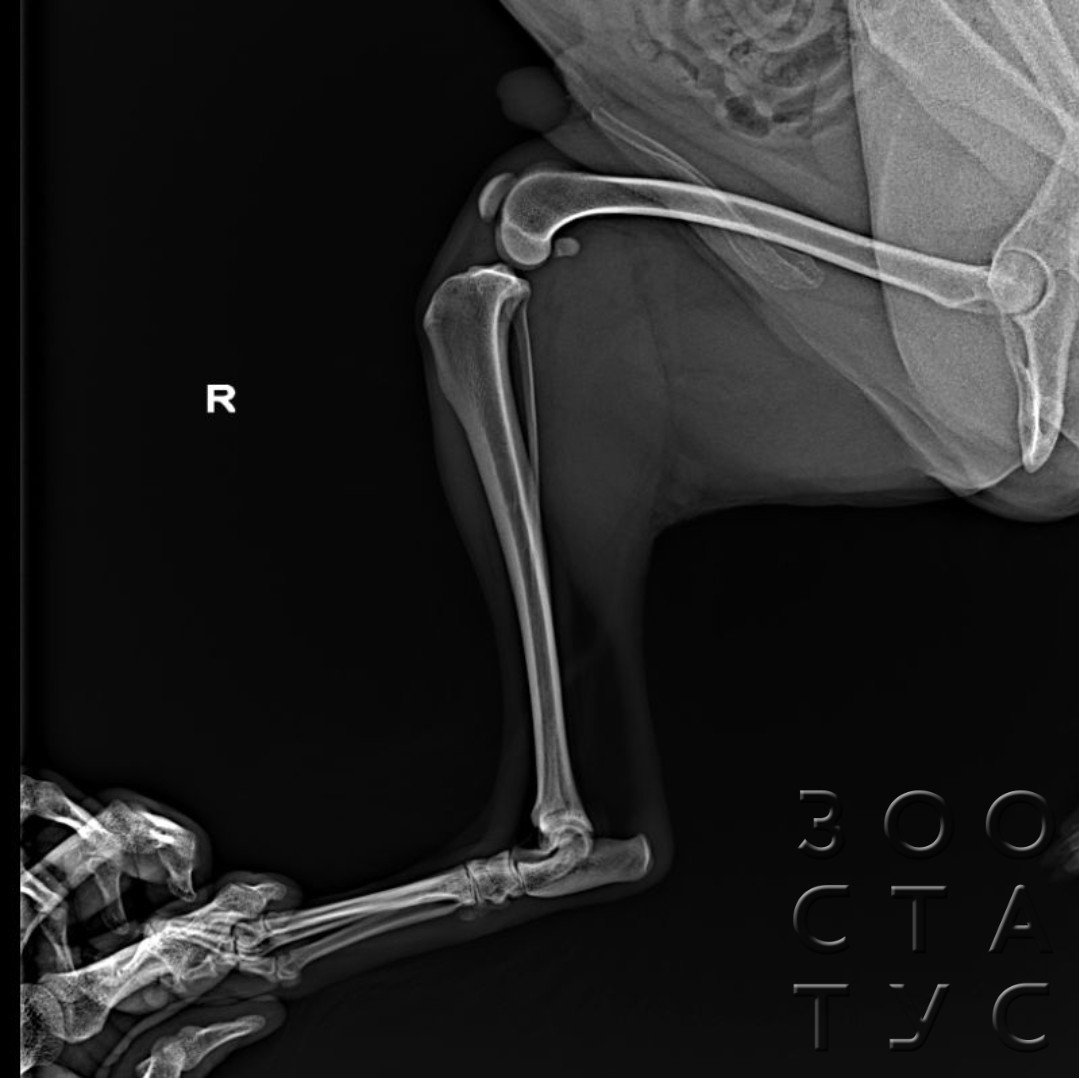

- при хромоте неизвестной этиологии, подозрении на переломы, вывихи, другие травмы, при ортопедических патологиях (болезнь Легга-Кальве-Пертеса, расслаивающем остеохондрите, остеоартрозе, дисплазии и тд);

- рентген лап рекомендуется для всех собак крупных и гигантских пород в возрасте от 4 месяцев для исследования на дисплазию тазобедренных и локтевых суставов;

- тест на дисплазию для РКФ проводится в возрасте 12-18 месяцев - для получения сертификата РКФ об отсутствии дисплазии суставов;

Рентгенография практически всех ортопедических патологий, и все исследования на дисплазию проводятся только под седацией, так как иначе невозможно грамотно расположить собаку для проведения исследования (в частности, при диагностике дисплазии тазобедренного сустава тазовые конечности должны быть параллельны, изображение костей должно быть полностью симметричным, иначе результаты будут недостоверны, такого положения невозможно добиться фиксацией владельцем у неспящего животного, даже если собака абсолютно спокойна). Седация необходима и агрессивным или напуганным животным, жесткие способы фиксации могут нанести гораздо больше вреда их здоровью, чем медикаментозный сон.

Для получения рентген-снимка на дисплазию для РКФ исследование собаки обязательно должно проводиться под седацией.